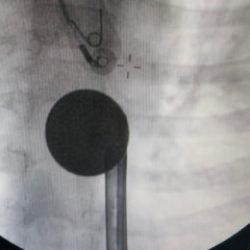

Ameliyatlarda yeni dönem! Neşterin yerini robot kolları alıyor

Cerrahi operasyonlarda kullanılan standart laparoskopik yöntemler, yerini ileri teknoloji ürünü robotik cerrahiye bırakıyor. Uzmanlar, cerrahın el titremesini ortadan kaldıran bu teknolojinin, hızlı iyileşme sunduğunu vurguluyor.